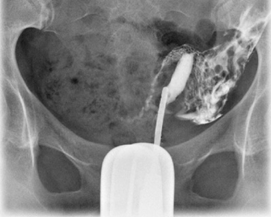

Unicornuate uterus

1 uterine horn

Typically associated with ectopic/undescended ovary.